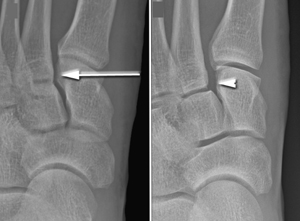

(Left) In this non-weightbearing x-ray, the Lisfranc injury does not show any abnormal widening (arrow). (Right) The tear of the Lisfranc ligament is more evident in this weightbearing stress x-ray, showing a widening of the joint.